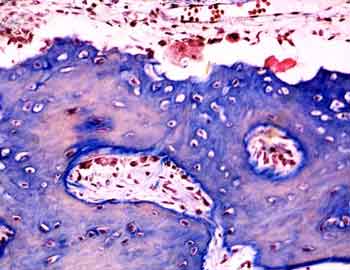

Visión específica: a mayores aumentos veremos matriz ósea, tras la desmineralización, de color azulado, y en su interior osteocitos. En la superficie de las trabeculas en formación ribetes epiteloideos de osteoblastos se encargan de ir incrementando el tamaño del hueso en formación. En otras áreas ya se han iniciado los mecanismos resortivos del hueso a expensas de la actividad de los osteoclastos, células multinucleadas gigantes de origen monocítico. El tejido circundante muy bien vascularizado esta poblado por células indiferenciadas que en las proximidades a la zona ósea en formación. Se tratan de elementos osteoprogenitores, y de ellas derivara todo el linaje de los osteoblastos, osteocitos y células de las superficies óseas, siendo estas ultimas las quiescentes a la espera de activarse como respuesta a la información que reciben del entorno, fundamentalemente de los osteocitos intramatriciales.